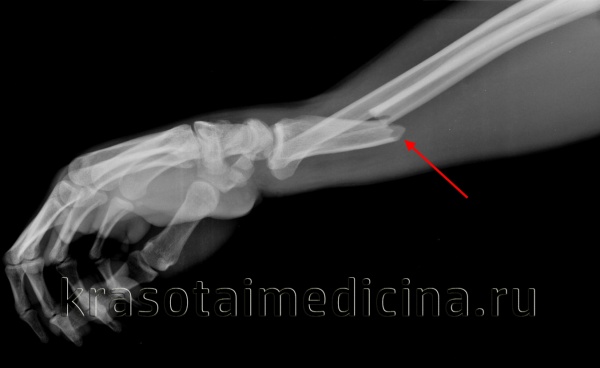

(Справа) На боковой рентгенограмме у восьмилетнею ребенка с повреждением после падения на вытянутую руку определяется перелом дистальною метафиза лучевой кости с тыльным изгибом кортикального слоя. В то время как ладонный кортикальный слой изогнут, но остается интактным. Отмечается ладонное положение дистального конца локтевой кости в сравнении с лучевой костью. (Слева) На передне-задней косой рентгенограмме у этою же восьмилетнего ребенка определяется переломовывих Галеацци с переломом дистальной трети лучевой кости с тыльным и лучевым смещением, а также вывихом дистальною лучелоктевою сустава с интактным дистальным концом локтевой кости.